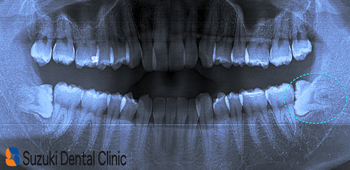

30代の男性、HPをご覧になって来院。主訴は「痛いので何件かの歯医者に行ったが、『ここでは抜けない』と断られた。土曜日しか時間の都合が合わないので、大きな病院では難しい。HPで検索(親知らず 大阪 名医/後日談)してここに来た」でした。(恐縮です)

Dr:「これは難しいですよ。理由は

①歯が歯肉に埋もれて見えない

②真横に生えている

③90度に根の先が折れ曲がっている

④口が大きく開かないので施術が困難

骨の中に埋もれている割合+横向き度合い+根の曲がり具合(左下の写真)→抜歯の難レベル(A→B→C→ウルトラC)から考えると“ウルトラC”に属します。